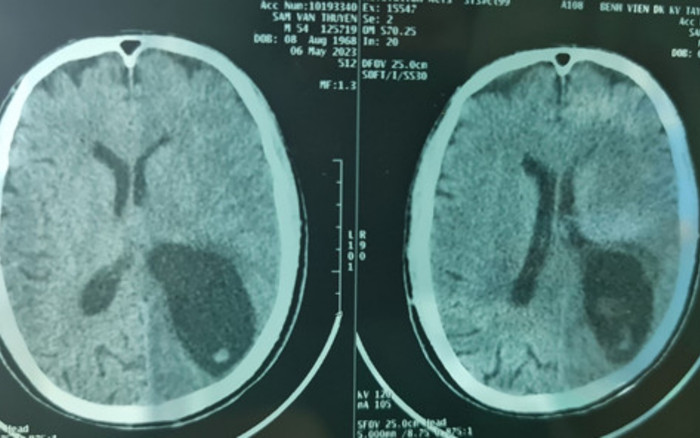

Hình ảnh chụp sọ não của bệnh nhân trước khi phẫu thuật. (Ảnh: BVCC).

Tại đây bệnh nhân đã làm các xét nghiệm phân tìm ký sinh trùng ( ), xét nghiệm Elisa chẩn đoán ấu trùng sán lợn Cysticercosis( ), chụp cắt lớp vi tính não cho thấy có nhiều ổ giảm tỷ trọng kèm phù não lớn vùng bán cầu trái.

Sau hội chẩn, các bác sĩ chẩn đoán bệnh nhân bị hội chứng tăng áp lực nội sọ do ấu trùng sán dây lợn trên hệ thần kinh, nguy cơ tử vong cao nếu không xử lý kịp thời.